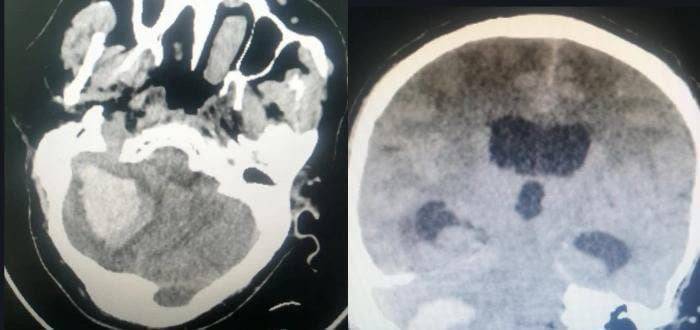

تمكن أطباء الأنف والأذن والحنجرة في منطقة جازان (جنوب السعودية) من إجراء تدخل جراحي معقد لترميم قاع جمجمة مريض في عملية معقدة استمرت لمدة 5 ساعات.

وقالت الصحة السعودية أن أطباء جراحة الأنف والأذن والحنجرة بمستشفى الملك فهد المركزي تمكنوا يوم الإثنين الموافق 12 سبتمبر من ترميم قاع الجمجمة الجانبي وأنسجة الدماغ والأذن لمريض عانى من تآكل شديد بعظمة ودهليز الأذن والقنوات الهلالية وصولاً لعظام القوقعة.

كما صرح الفريق الطبي المعالج للحالة أنه استخدم خلال العملية المايكروسكوب الجراحي وجهاز ملاحة الأعصاب لترميم كامل قاع الجمجمة الجانبي من خلال الأذن وفصل التجويف الدماغي عن الأذن وترميم عظامها الدقيقة كذلك.